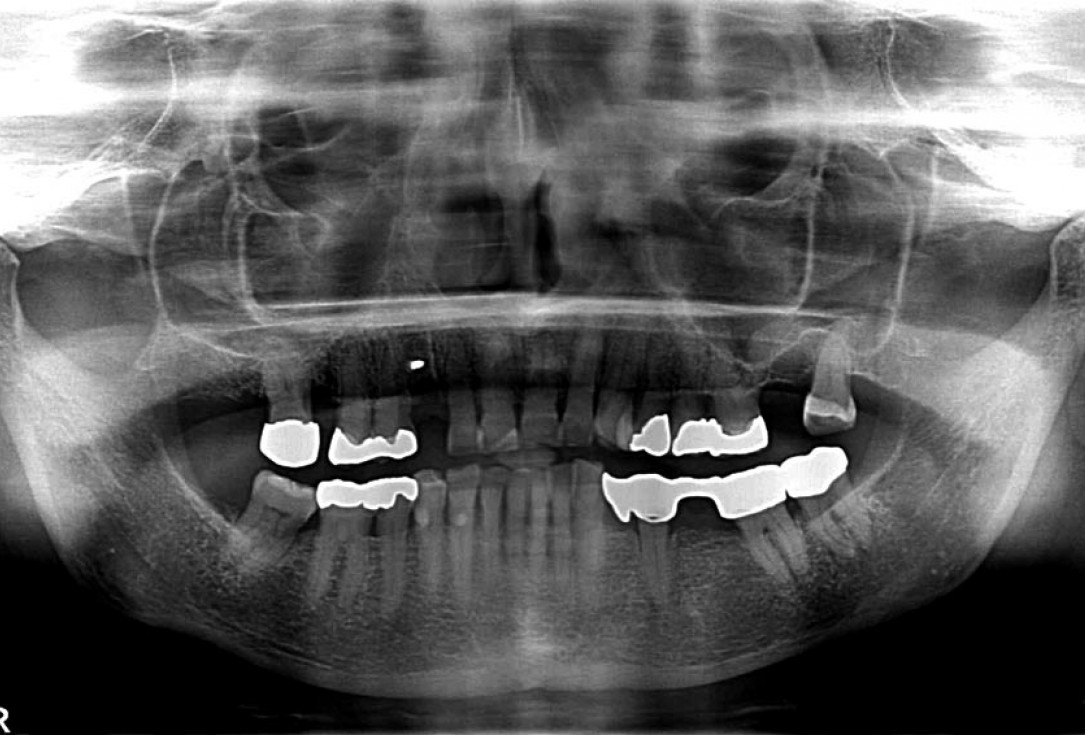

10/12 - X-ray scan after implant placement

Block augmentation with maxgraft® in the maxilla - PD Dr. Dr. F. Kloss